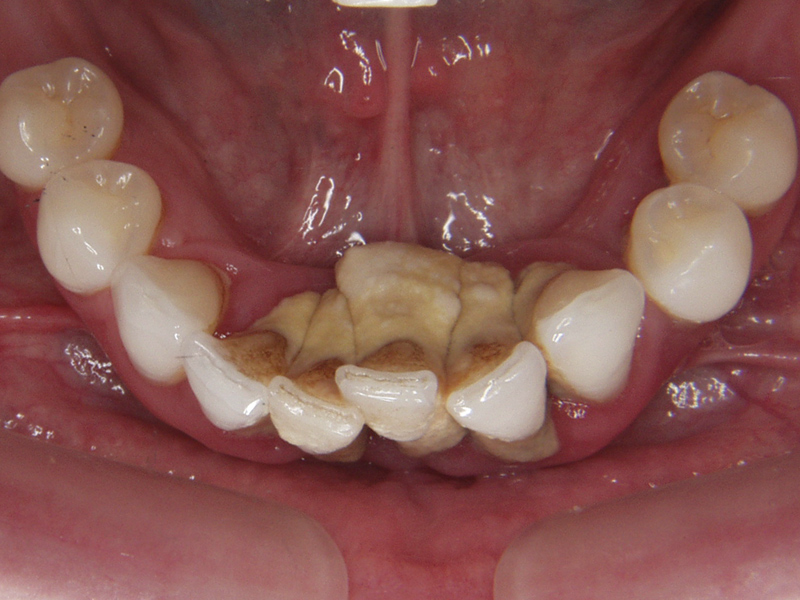

Implant soft tissues attach at much deeper levels when compared with where the attachment of soft connective tissue exists with the natural dentition. The platform of an implant is frequently related 3 mm below the facial free gingival margin to facilitate an emergence profile of the restoration. Where papillae exist, this relates often to depths closer to 5 mm to 7 mm.10 This is of concern from the standpoint of maintenance because, generally, it is not possible to efficiently clean deeper than 4 mm with scaling instruments11 and because the microbiota at this level tend to favor anaerobic Gram-negative bacteria, which can result in peri-implant disease.

Many of the newly designed, narrower implant systems available today no longer use the free gingival reference marker, and it has been suggested that placement of the head of the implant be 1 mm to 2 mm below the crest of the marginal bone. This further increases implant depth and provides an environment more conducive for these anaerobes.

Restoration Depth

With regards to the natural dentition, cemented restoration margins are recommended for placement not more than 0.5 mm into a healthy gingival sulcus,12 but even that minimal depth is considered a compromise of tissue health. Current clinical recommendations allow clinicians to place cementation margins of implant-supported restorations up to 2 mm subgingivally.13 This is commonly done to hide the abutment–crown interface, to accommodate possible peri-implant tissue recession with time, or to achieve a more natural emergence profile. Linkevicius et al reported on the influence of cementation margin position and the amount of undetected cement;14 they found that all cement remnants could be removed only when supragingival margins existed and concluded that implant abutments should have visible margins for intraoral cementation.